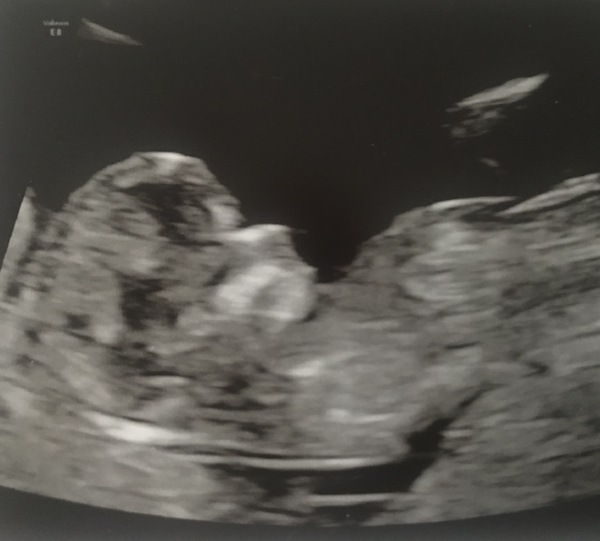

Aw I'm loving all the scan pics, it's so lovely to see and I think maybe a sign that some of us are starting to feel a bit more ... Maybe comfortable? Definitely not relaxed, possibly hopeful is a better word. So I thought I'd join in, here's our little goblin at 9+4 from Friday (note the pointy ears... dH says elf but it's given me so much trouble I think it has to be a goblin)

Pregnant after loss and dreaming of rainbows....